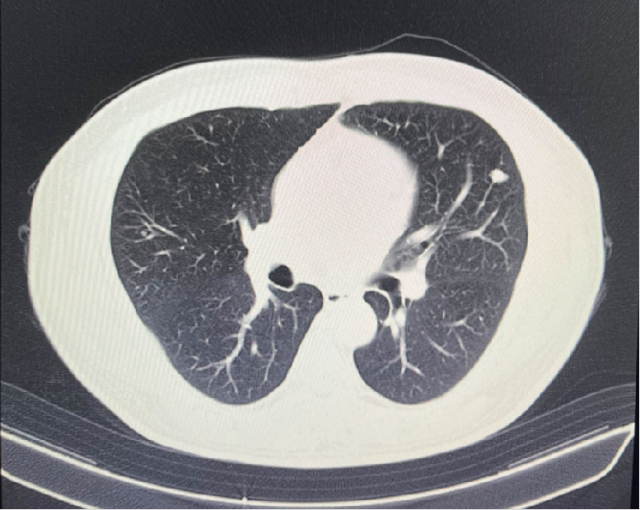

影像学检查

2023-11-08: